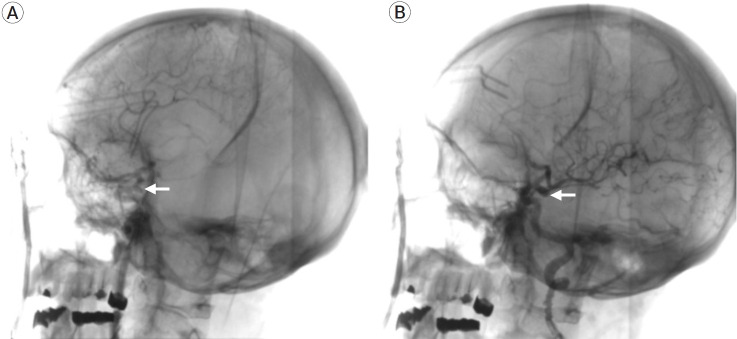

Bilateral posterior communicating (pComm) artery aneurysms represent only 2% of mirror intracranial aneurysms. Usually, these are surgically approached through bilateral craniotomies for clipping. We present the case of a 50-year-old female presenting with headache and horizontal diplopia. Neurological examination revealed a left oculomotor palsy, with no other neurological deficits. Imaging studies revealed bilateral aneurysmatic lesions in both internal carotid arteries (ICA). A conventional left pterional approach was planned in order to treat the symptomatic aneurysm, and, if deemed feasible, a contralateral clipping through the same approach. The procedure was performed in a hybrid operating room (HOR), performing an intraoperative digital subtraction angiography (DSA) and roadmapping assistance during dissection and clipping. Transoperatively, a post-fixed optic chiasm was identified, with a wide interoptic space, which allowed us to perform the contralateral clipping through a unilateral approach. This technique for clipping bilateral pComm aneurysms can be performed when the proper anatomical features are met.